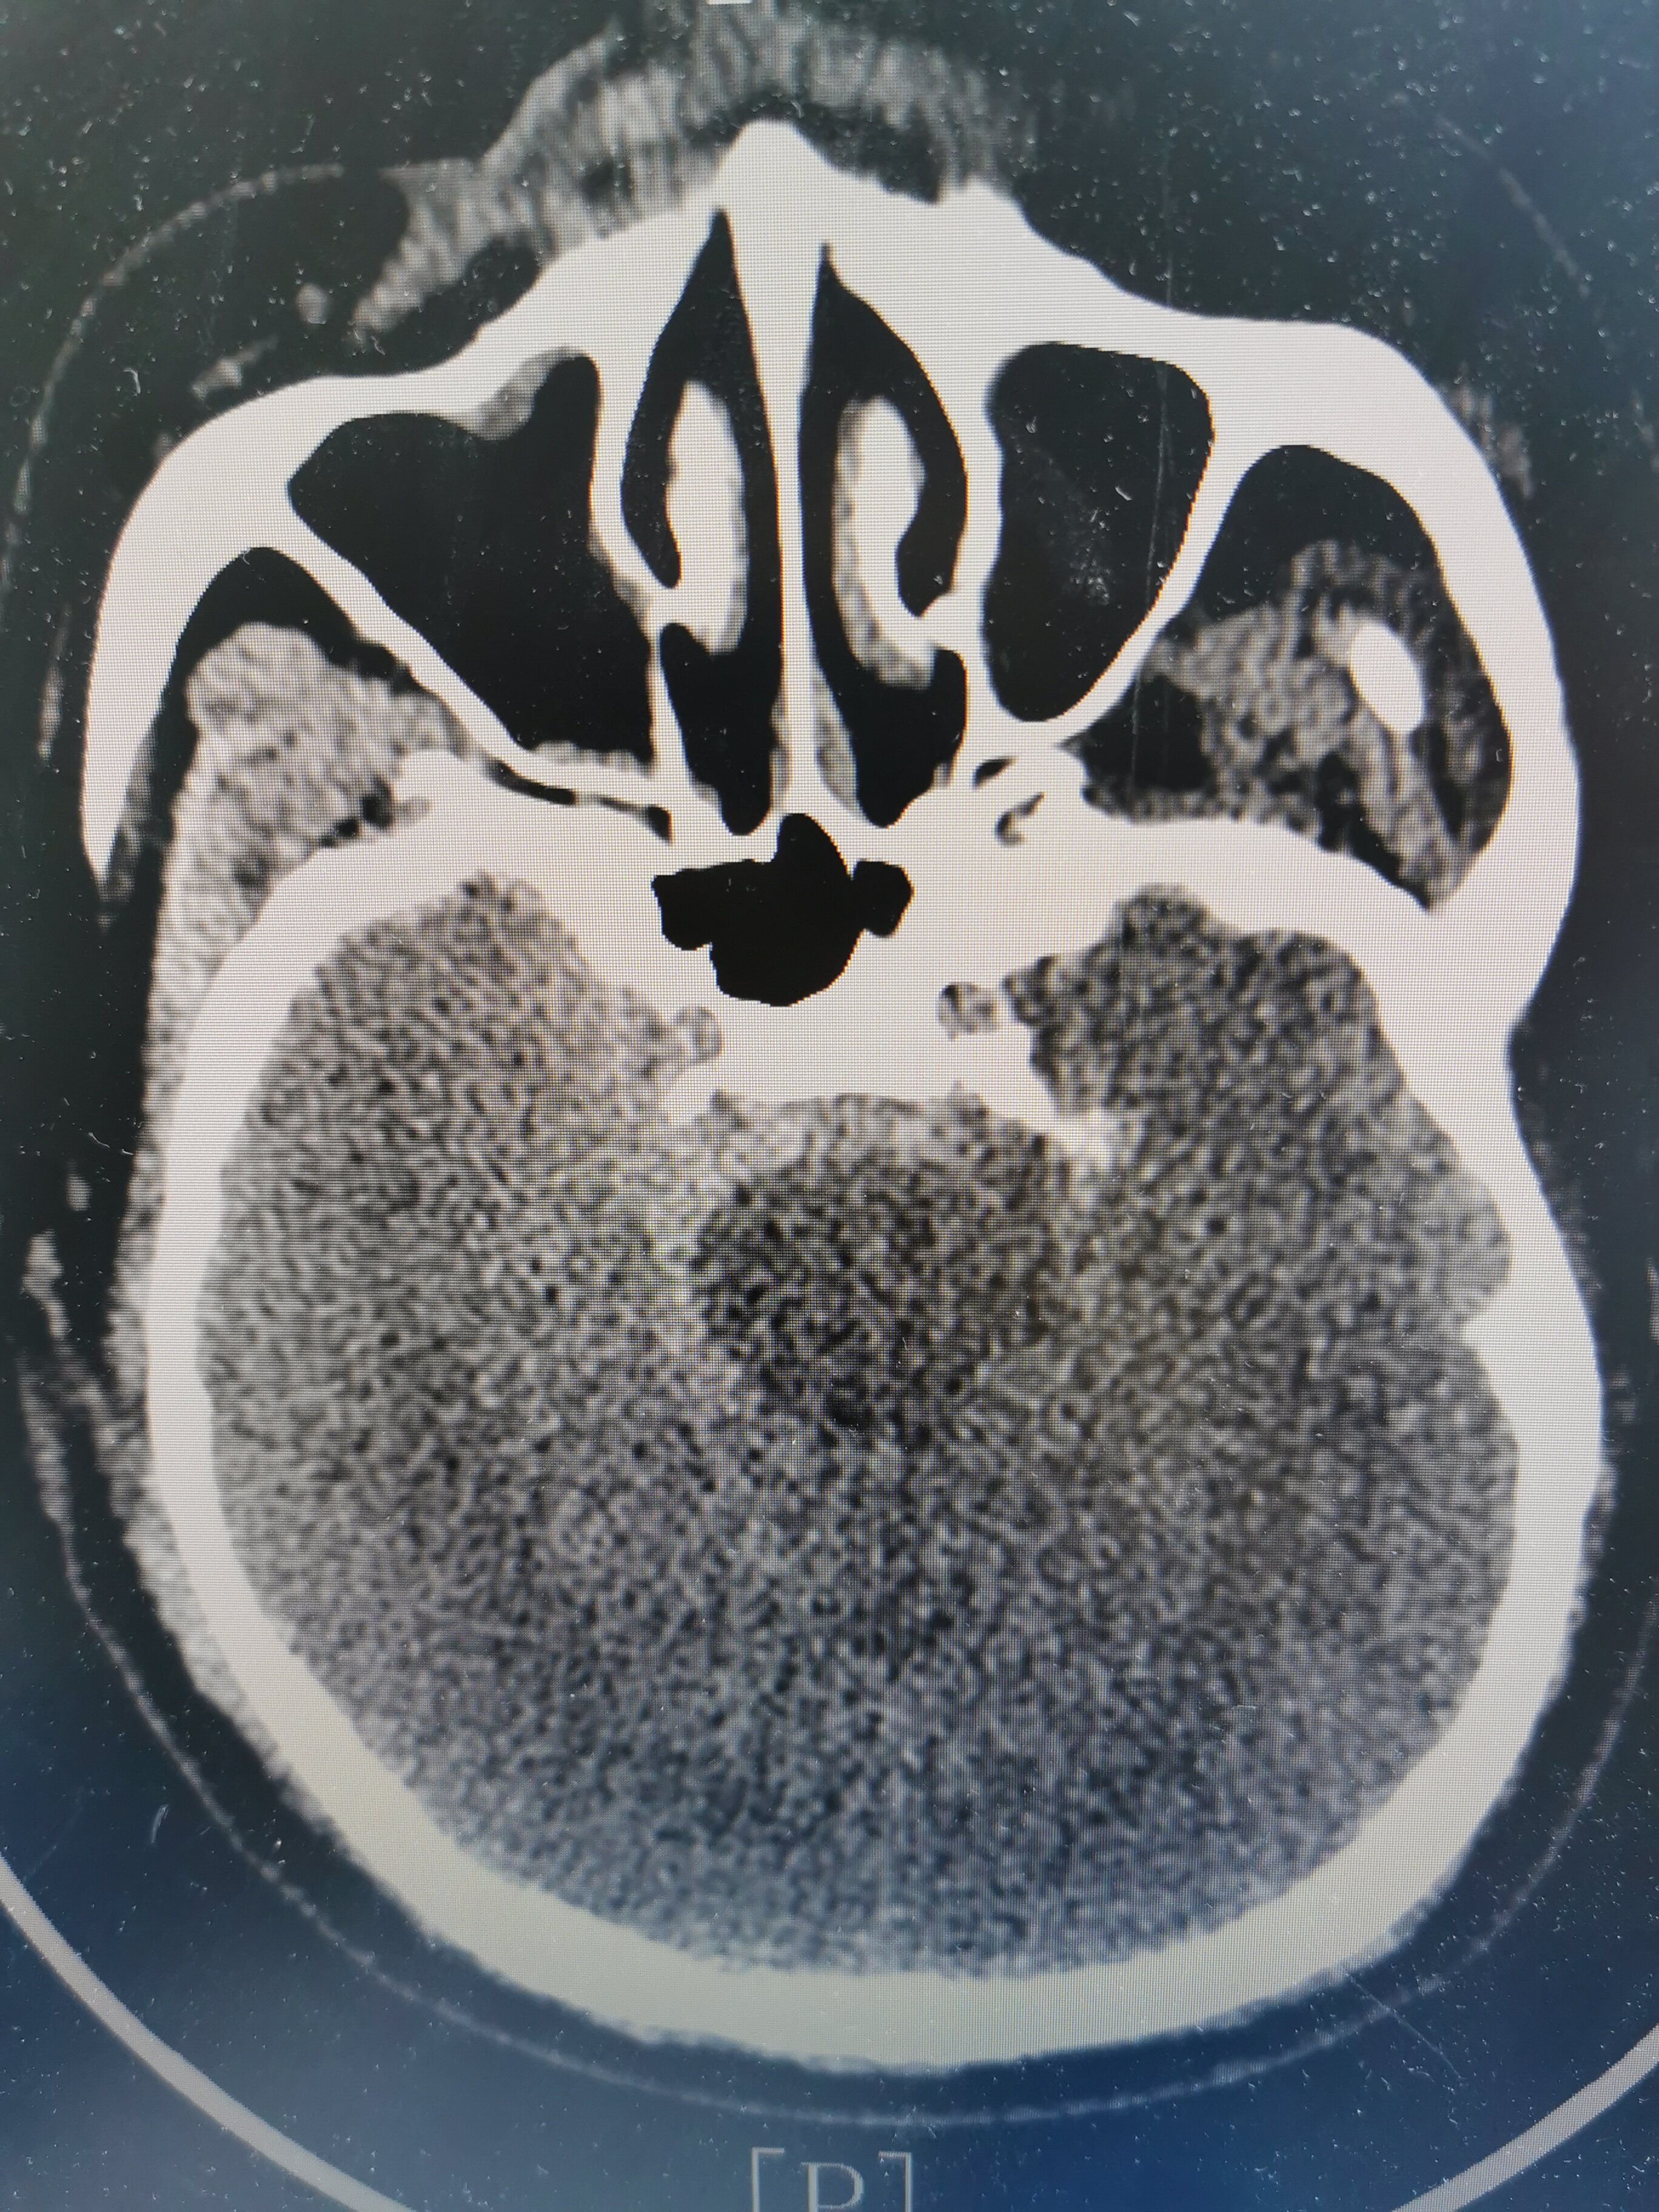

59岁男性患者,突发动脉瘤破裂出血1小时余, hunt

急送至安徽省某三甲医院,查头颅ct示蛛网膜下腔出血